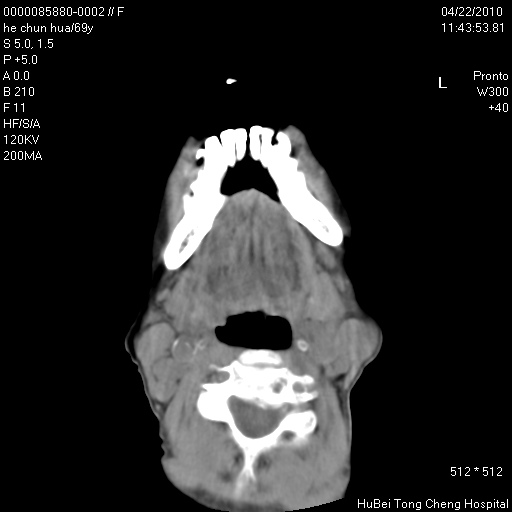

标题: CT25937:女,69Y

硬腭部包块十余年,渐进性增大。